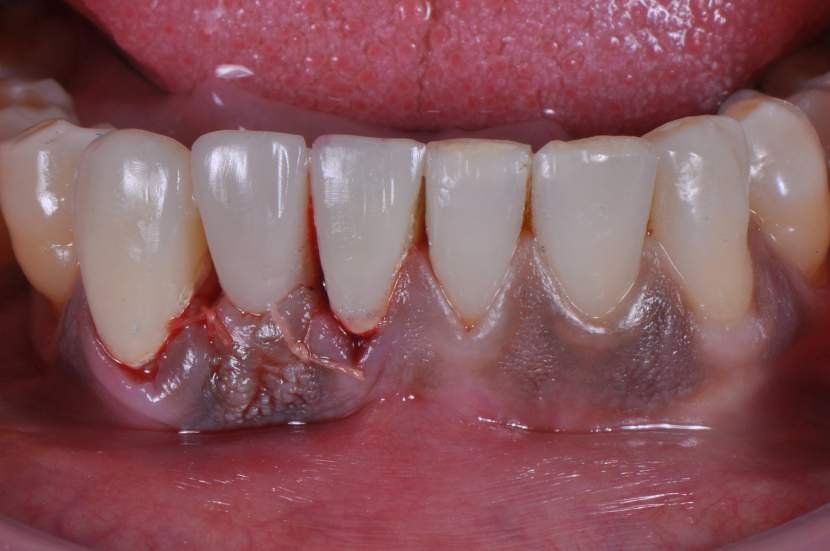

Implantes estreitos de titânio surgiram na Implantodontia com a indicação clássica de serem utilizados para substituição de incisivos laterais superiores, incisivos inferiores (Fig.1), espaços edêntulos pequenos e com baixa incidência de carga mastigatória.

CASO CLÍNICO

Paciente com perda do incisivo central inferior do lado direito, utilizando uma prótese fixa em zircônia com estética e adaptação deficientes.